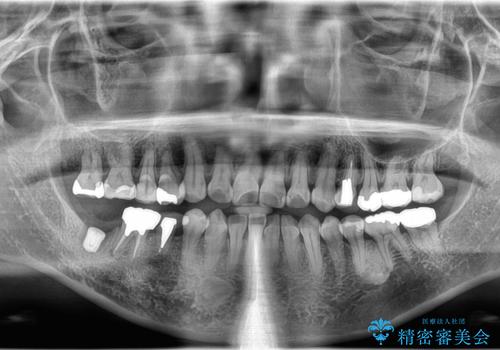

- 食事の度に、歯の中に物がつまるとのことで来院された患者様です。

精密検査を行った結果、歯が折れていたため保存は難しく、インプラント治療になりました。

現在は、違和感なども無くなり、固いものも食べられると喜ばれていました。

インプラント治療をすることによってしっかりと噛めるようになりました。